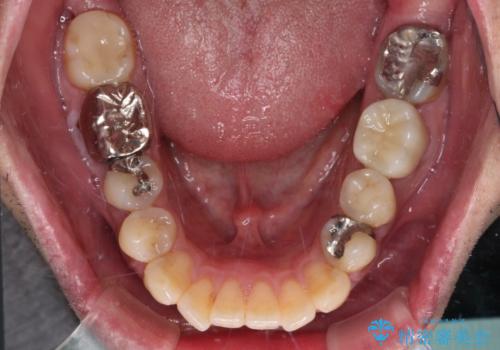

欠損と痛み 奥歯のむし歯治療

下顎の根管治療がされた大臼歯は咬合時に痛みが認められたため、再度根管治療を行った後に補綴治療することとしました。